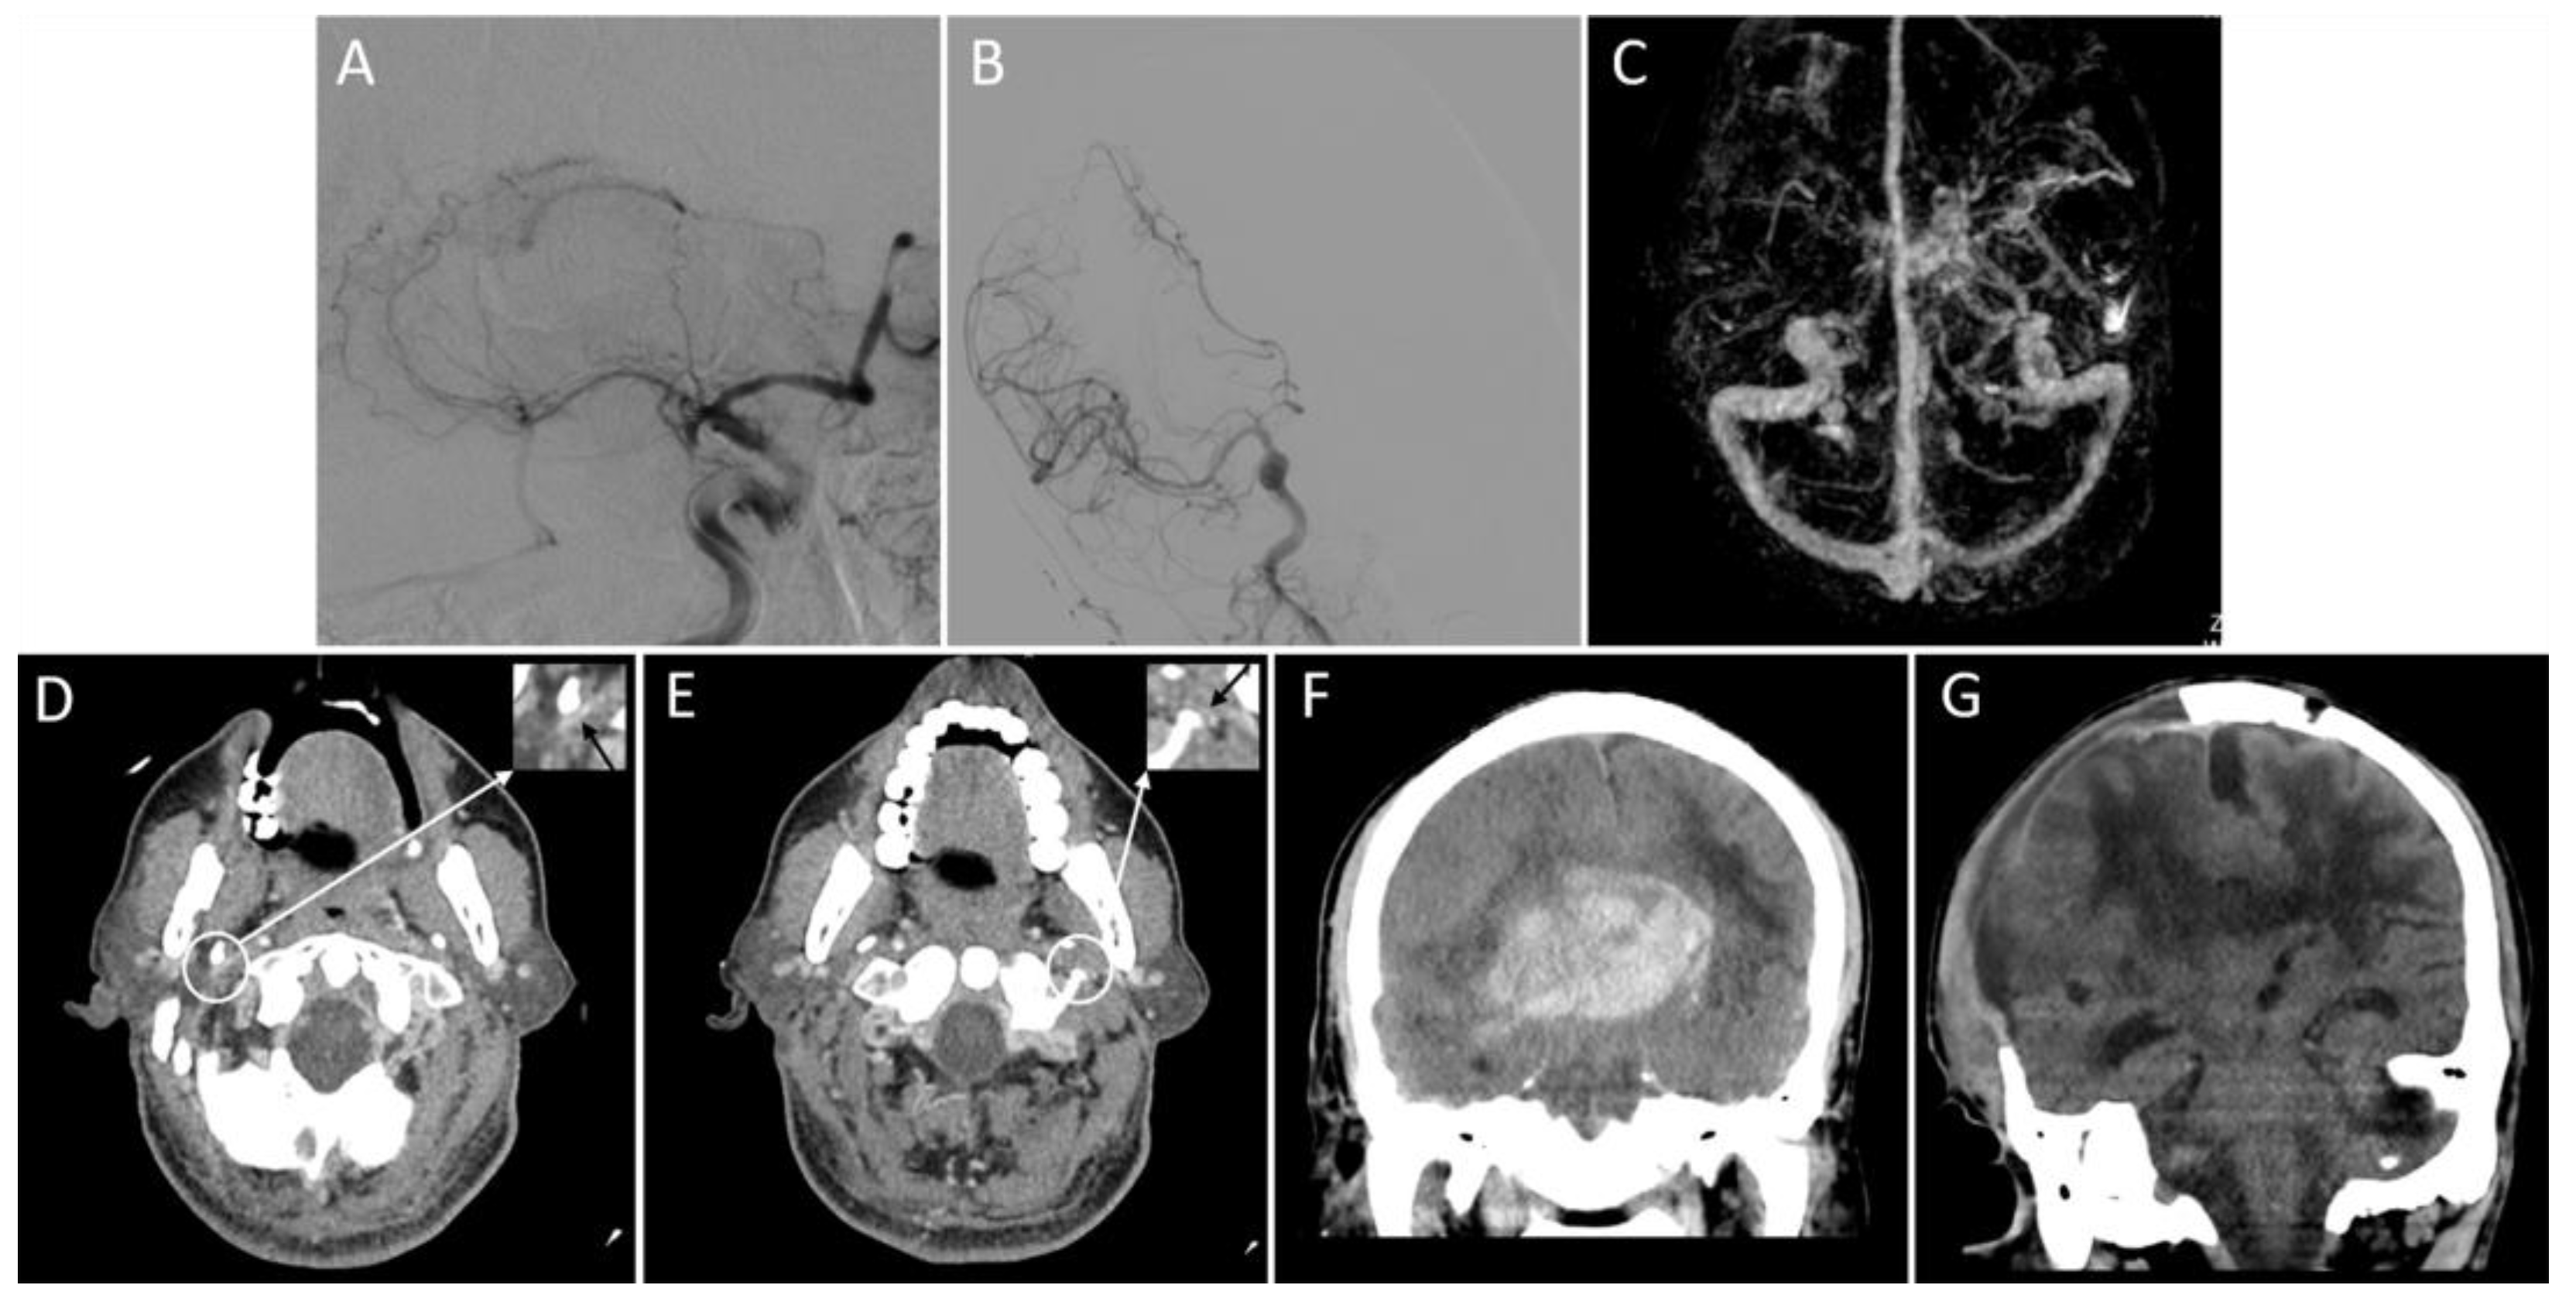

2.2. Image Analysis